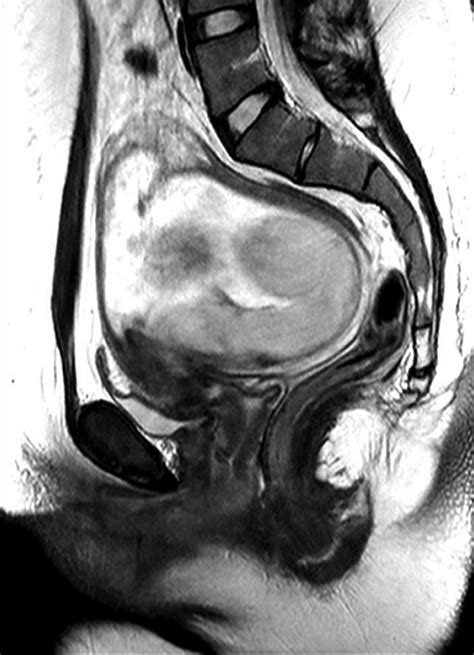

A retroflexed uterus, also known as a tilted uterus, is a condition where the uterus is angled backward towards the spine instead of forward towards the bladder. This condition is relatively common and is often discovered during routine gynecological examinations. It is important to understand that a retroflexed uterus is a normal anatomical variation and does not always cause symptoms or require treatment.

A retroflexed uterus is typically diagnosed during a routine pelvic examination. The healthcare provider may feel the uterus tilted backward during the exam. Additional diagnostic tests may include:

• Magnetic Resonance Imaging (MRI): An MRI can provide detailed images of the pelvic organs.